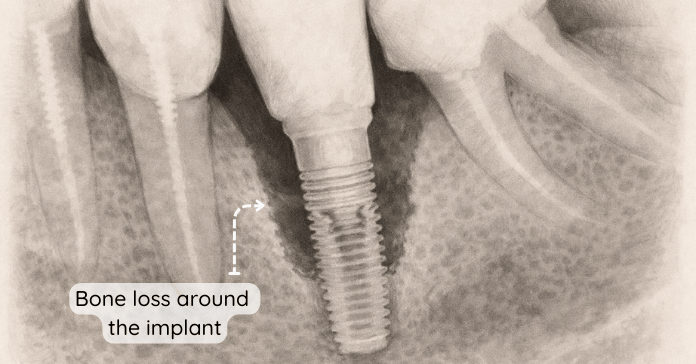

There are two main types of dental implant infection, known as peri-implant mucositis and peri-implantitis. Peri-implant mucositis affects only the gum tissue around an implant and causes redness, swelling, and bleeding without bone loss. If left untreated, it can progress to peri-implantitis, which is a serious infection that damages the bone around the implant.

This advanced condition increases the risk of implant failure if not treated promptly. Understanding this difference helps you act early and protect your tooth implant before permanent damage occurs.

- Visible Bone Loss on X-ray: Progressive bone loss around the implant confirms advanced peri-implantitis.

Dental X-rays reveal bone loss around the implant and show whether the infection has spread deeper. Early diagnosis improves implant success and allows targeted implant infection treatment before permanent damage occurs.

In severe cases of peri-implantitis, dentists perform surgical procedures to access and clean infected implant surfaces. They remove inflamed soft tissue and disinfect the area thoroughly to control infection around the implant. If bone loss is present, bone grafting may rebuild support around an implant and improve stability.